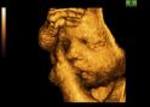

When does an unborn baby become human? If our contradictory laws are to be believed, it all depends on geographical location and whether or not the wrong person tries to kill him. A case in point comes to us from Wisconsin, where a man, Manishkumar Patel, is being charged with first-degree murder for slipping the abortion drug RU-486 into his pregnant mistress’ drink.

The contradiction here should be obvious. If the thesis used to justify legalized abortion is correct — that an unborn baby is merely an "unviable tissue mass" — how can Patel be guilty of murder? And if the baby is human, as the murder charge implies, how can abortionists not be?

This is what explains such a complete descent into irrationality. An unborn baby is either human at a given stage of development or he isn’t. Under our paradigm, however, his humanity is a fluid thing, determined by time, place and circumstance. If one parent wants him and the other wants him dead, he’d better hope the latter is not the member of the group that has been given a license to kill.